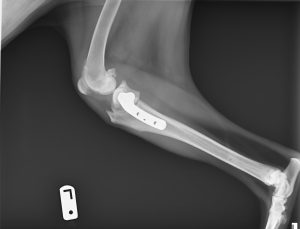

Also, one of my dogs had TPLO surgery on both back legs last year. I don’t want to talk about how much it cost (but I do affectionately call her my bionic dog, AKA the six-million-dollar dog, now), but at least she’s 100% healed and can take walks and swim again. I’m going to be a worrywart for a while every time she does anything remotely active, but I’m trying to give her a little freedom. Here’s one of her x-rays so you can see what they did to her legs (cut the bone, realign and attach with a metal plate and screws):